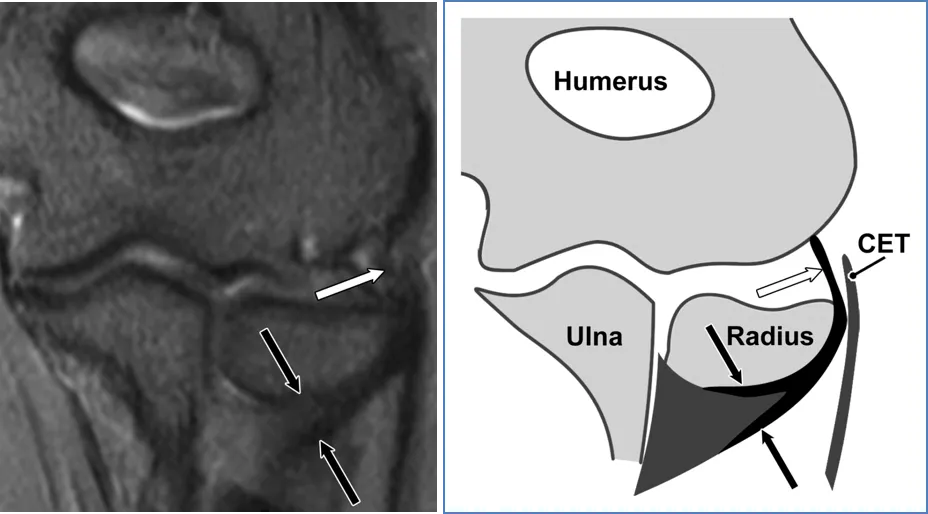

(a)27岁女性的冠状STIR磁共振成像。外侧尺侧副韧带近端(白色箭头)和远端(黑色箭头)信号强度正常。(b) 对应的外侧尺侧副韧带示意图显示了近端(白色箭头)和远端(黑色箭头)两个方面。CET = 伸肌总腱。